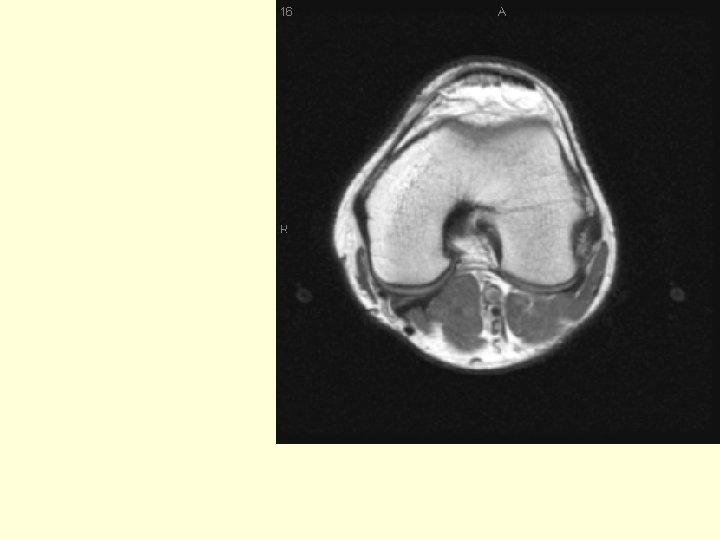

Why don’t we see any bones on this image? Because we are at the level of the knee joint